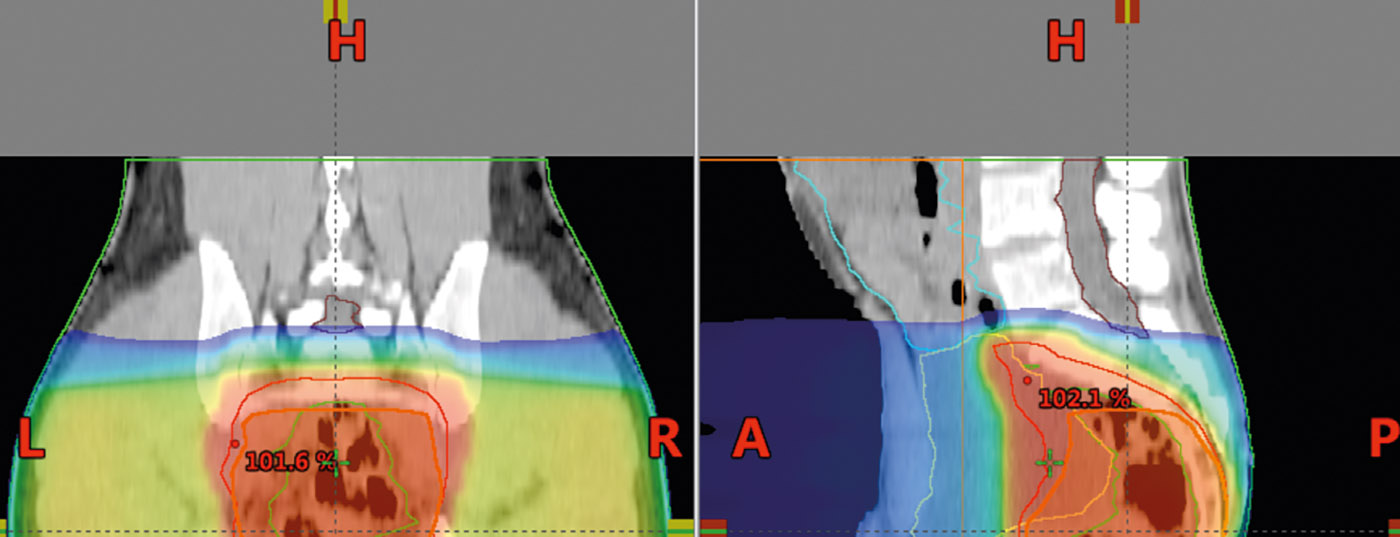

Analog zur S3-Leitlinie der DKG 2014 können stadiumabhängig Empfehlungen getroffen werden. Stadium I: Hier ist die alleinige totale mesorektale Exzision (TME) Standard. Stadium II und III: Die präoperative Radio(chemo)therapie ist Standard in der Behandlung des lokal fortgeschrittenen Rektumkarzinoms. Diese Therapie halbiert die Lokalrezidivrate, unabhängig vom Operationsverfahren. Wenn eine Langzeittherapie als Radiochemotherapie vorgesehen ist, sollte die Chemotherapie 5-FU basiert sein. Die Langzeit-Radiochemotherapie führt zu einem Downsizing und Downstaging und ermöglicht damit eine bessere Operabilität.